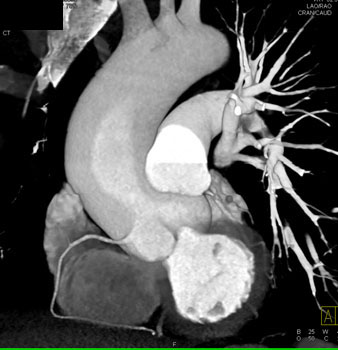

|  | Question 1: 46 year old male with atypical chest pain. What’s the best diagnosis based on the image set? |